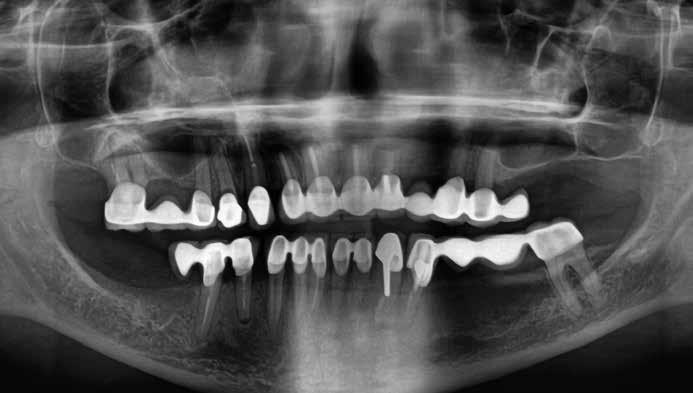

Cikkünkben összesen négy, kétrészes kerámiaimplantátum klinikai és radiológiai eredményeit mutatjuk be, amelyeket a felső, moláris régióba helyeztünk be.

A műtéti tervezéshez mindkét esetben CBCT-felvételt használtunk, majd az utánkövetési időszakban periapikális röntgenfelvételekkel ellenőriztük az implantátumokat. A fogeltávolítást követően azonnali implantáció történt, az alveolus fala és az implantátum felszíne közt fennmaradó réseket csontpótlóval töltöttük ki. A három hónapos gyógyulás leteltével az ideiglenes koronákat eltávolítottuk, A-szilikonnal lenyomatot vettünk, majd három lítium-diszilikát és egy monolitikus cirkónium-dioxid korona készült. A páciensek utánkövetése mindkét esetben minimum tizenkét hónap volt, amelynek során valamennyi implantátumot klinikailag és radiológiailag is sikeresnek ítéltünk az osszeointegráció, a marginális csont stabilitása és a periimplantáris szövetek egészsége tekintetében.

heléssel vagy anélkül). Az első páciensnél gyökérreszorpció miatt szükségessé vált a jobb felső premolárisok és az első moláris eltávolítása (1. a–b ábrák). A második páciensnél a bal felső második premoláris frakturát szenvedett (1. c–d ábrák) Az átfogó tervezést és diagnosztikát CBCT-felvétel segítségével végeztük (2. a–c ábrák), a posztoperatív kontroll és az utánkövetés időszakában pedig periapikális röntgenfelvételeket készítettünk. A jelen tanulmányban résztvevő valamennyi páciens nemdohányzó volt, jó, vagy gyógyszeresen jól karbantartott általános egészségi állapotnak örvendett. A hatékony plakk-kontroll ellenére műtét előtt mindkét páciensnél végeztünk supragingivális depurálást és gyökérsimítást.

A végleges ragasztást követően röntgenfelvételt készítettünk, amelyet összevetettünk a közvetlenül a műtét után készült felvételekkel: a marginális csontszint változatlan volt. A pácienseket 14 hónapon keresztül rendszeresen visszahívtuk. Klinikai és röntgenvizsgálattal sem tapasztaltunk komplikációt (12. a–b ábrák)

10. a ábra: Végleges lítium-diszilikát koronák. – 10. b ábra: Végleges monolitikus cirkónium-dioxid korona. – 11. a–b ábrák: Klinikai megjelenés tizenkét hónap elteltével. 12. a–b ábrák: Tizenkét hónapos kontrollröntgen-felvételek.